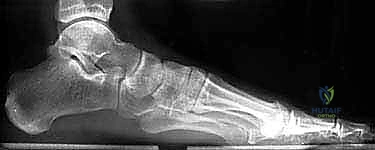

- الأشعة السينية (X-rays) متعددة الزوايا: لتقييم الانهيار العظمي وزوايا الكعب (مثل زاوية بوهلر وزاوية جيسان).

- الأشعة المقطعية ثلاثية الأبعاد (3D CT Scan): وهي الخطوة الذهبية والأهم في عيادة الدكتور هطيف. تتيح هذه الأشعة بناء نموذج ثلاثي الأبعاد دقيق للكعب المشوه، مما يسمح بتحديد أماكن الانحشار العظمي بدقة المليمتر، ومعرفة مدى تلف الأسطح المفصلية. بناءً على هذه الصور، يتم وضع خطة "القطع العظمي التصحيحي" قبل دخول غرفة العمليات.

إذا كان الكعب قد فقد ارتفاعه أو انحرف بشكل كبير، يقوم الدكتور هطيف بإجراء قطع دقيق في عظم الكعب لإعادة توجيهه إلى محوره الميكانيكي السليم. يتم استخدام طعوم عظمية (Bone Grafts)—تؤخذ غالباً من حوض المريض أو طعوم صناعية—لرفع الكعب المنهار واستعادة زاوية بوهلر الطبيعية.